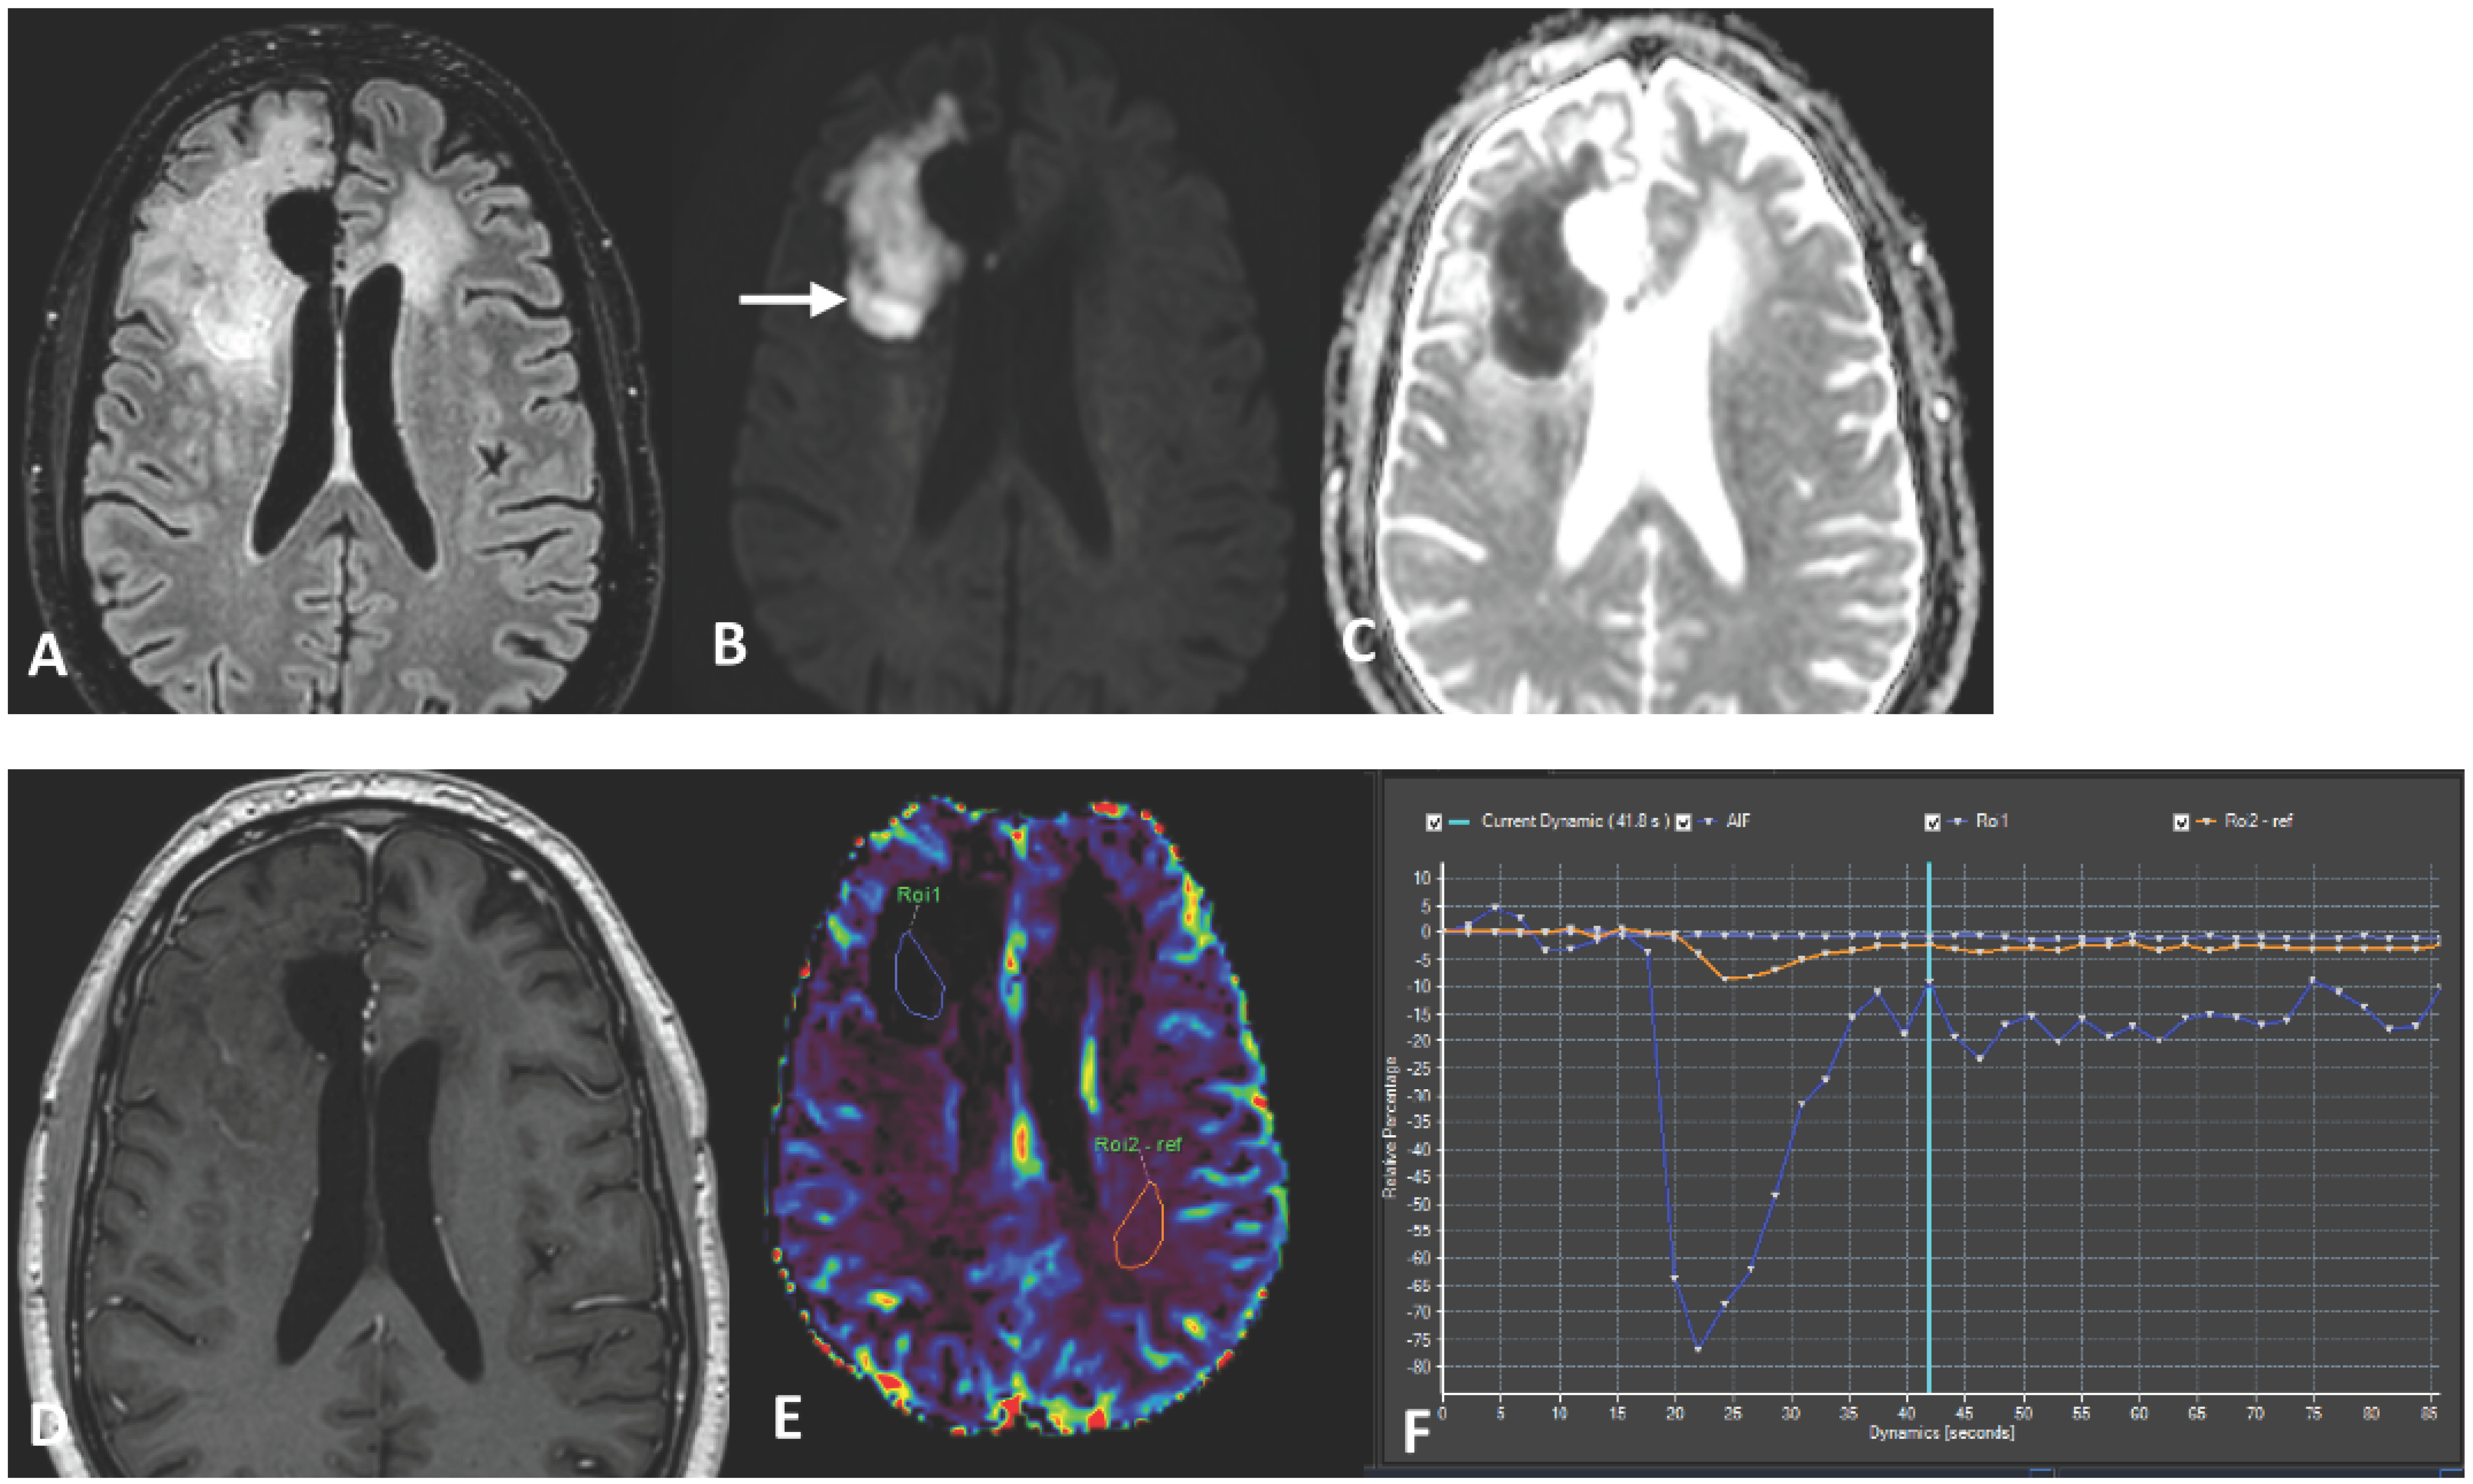

2. Case Report